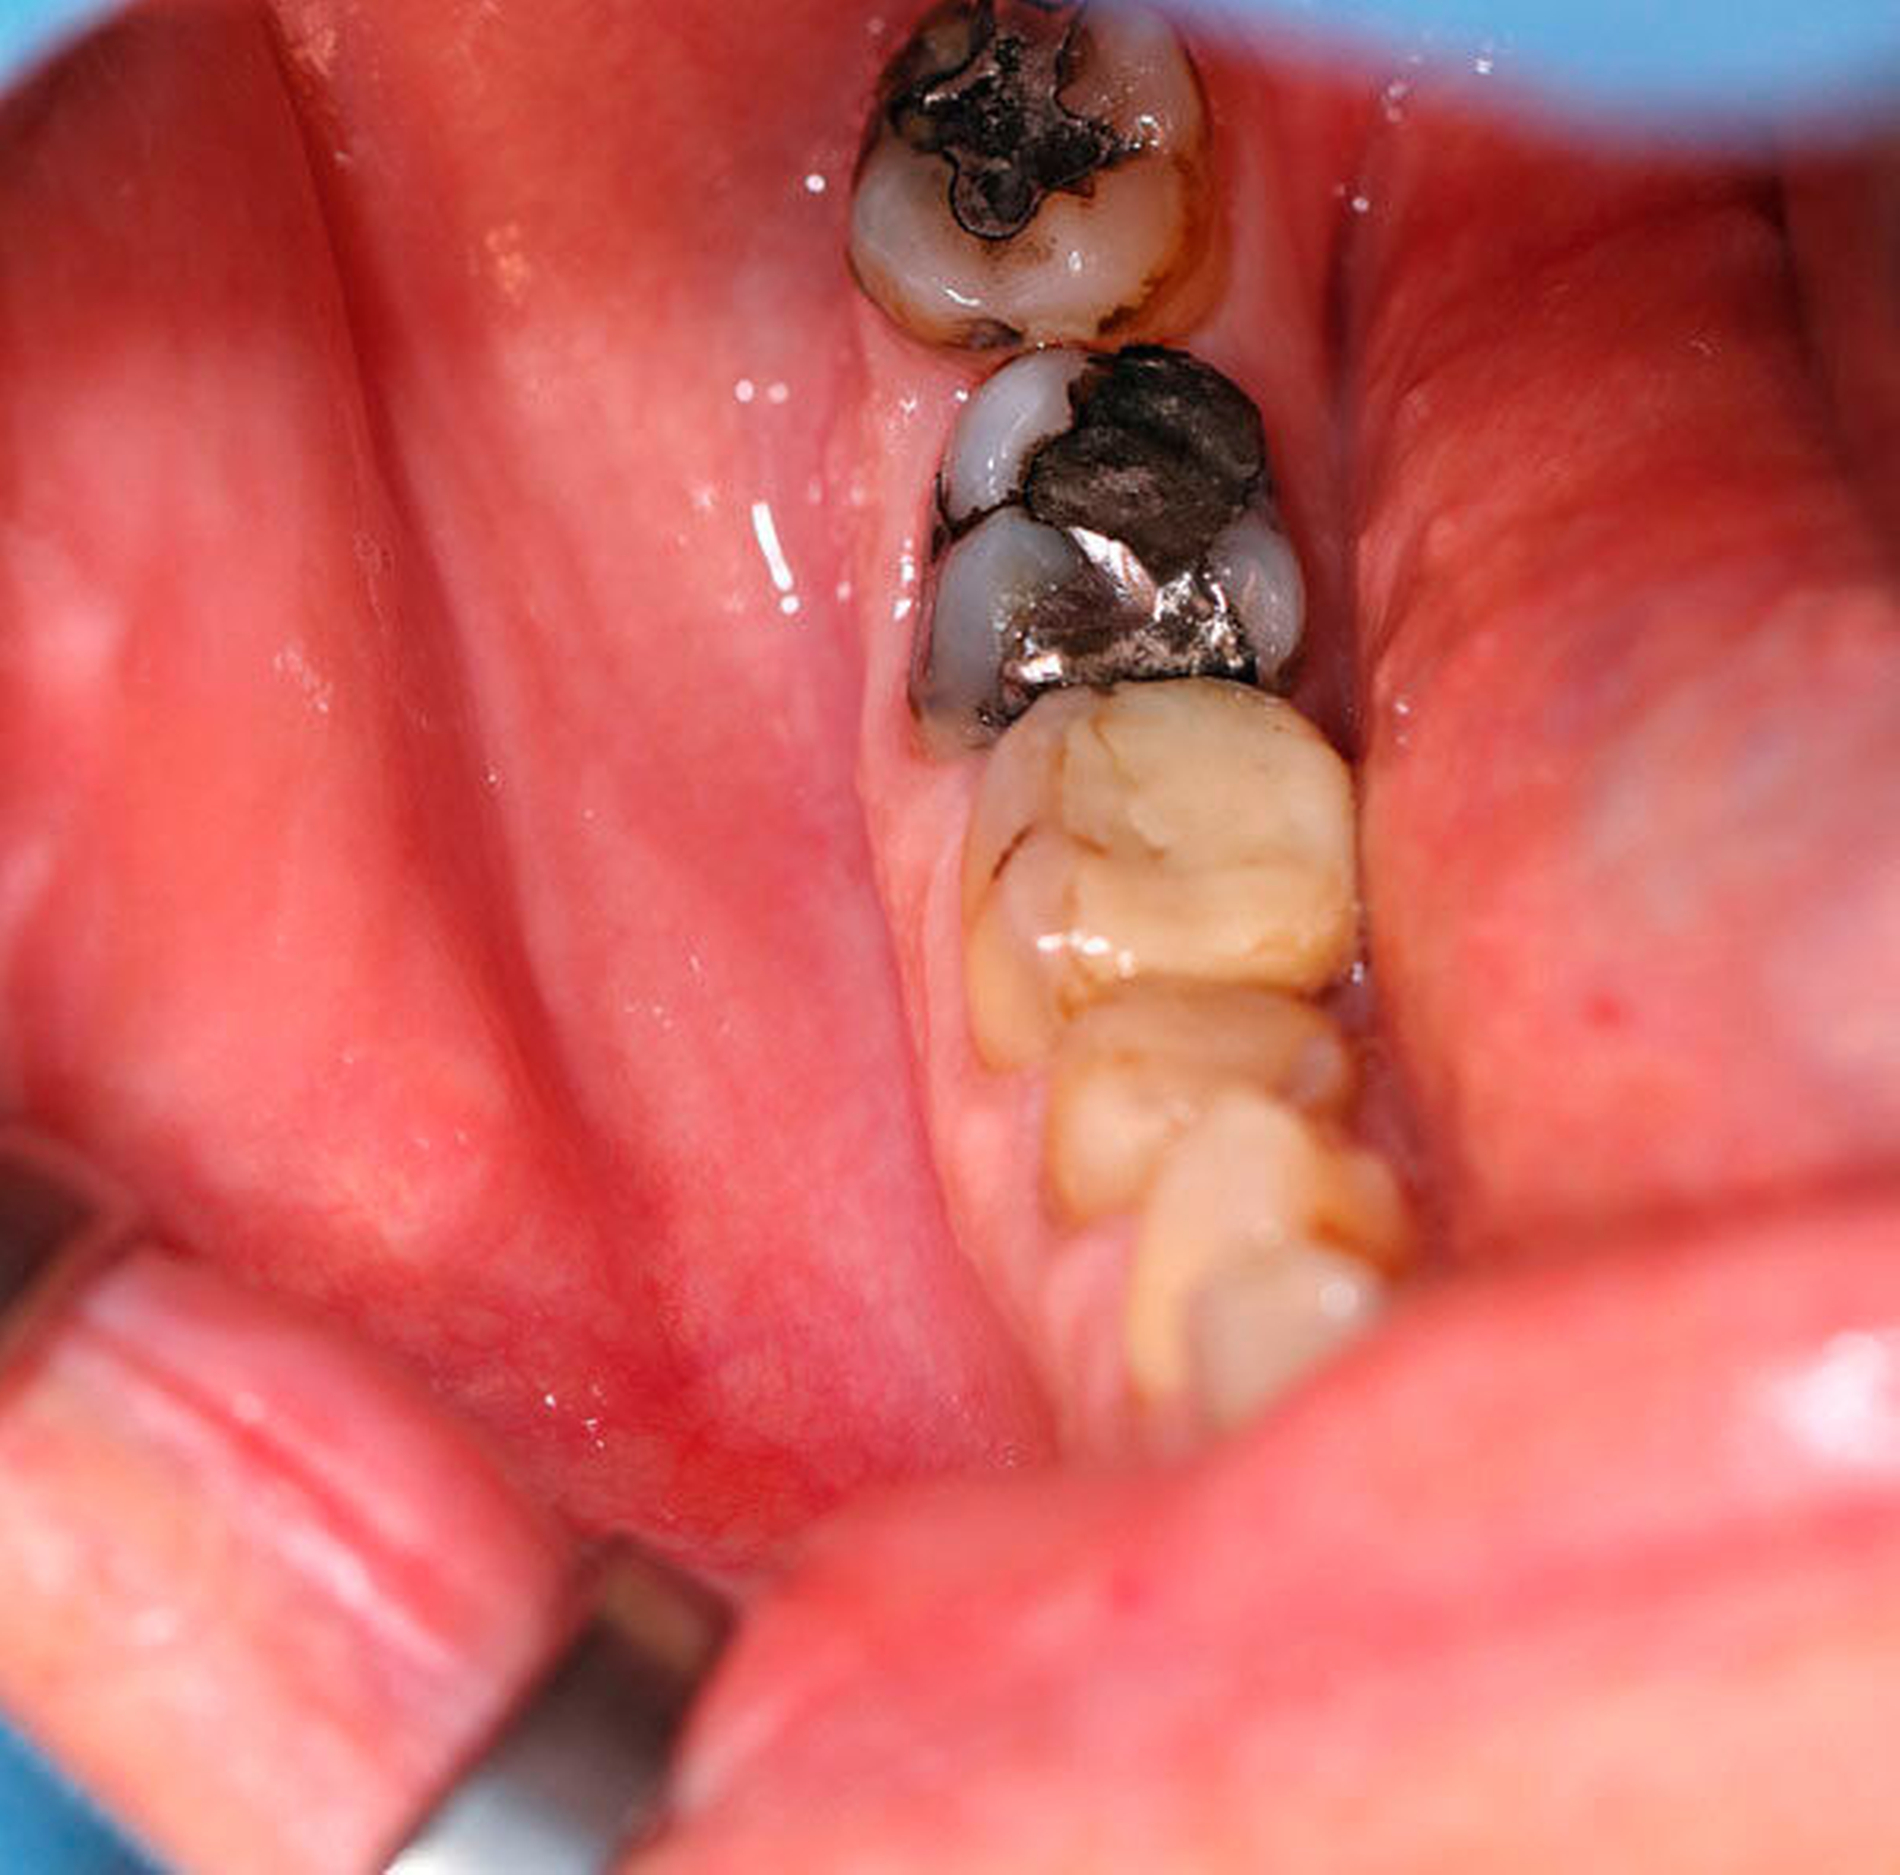

Auf der alio loco durchgeführten Panoramaschichtaufnahme (Abbildung 1) war eine ausgeprägte, zystische Raumforderung mit einer Ausdehnung von Regio 46 bis Regio 48 zu erkennen. Klinisch zeigten sich keine Sensibilitätsstörungen im Bereich des Nervus alveolaris inferior. Die Vitalitätsprüfung der Zähne 46 bis 48 fiel positiv aus, es bestand auch keine Perkussionsempfindlichkeit (Abbildung 2). Zahn 48 fiel durch eine drittgradige Lockerung auf. Auf Palpation entleerte sich kein Pus. Die anschließend durchgeführte Digitale Volumentomografie (Abbildung 3) zeigte einen invasiv wachsenden, teils honigwabenähnlichen, zystischen Befund des rechten Unterkiefers mit einer Ausdehnung in den Canalis mandibulae sowie in Teile des aufsteigenden Unterkieferasts. Darüber hinaus ließen sich Wurzelresorptionen der Zähne 47 und 48 eruieren.